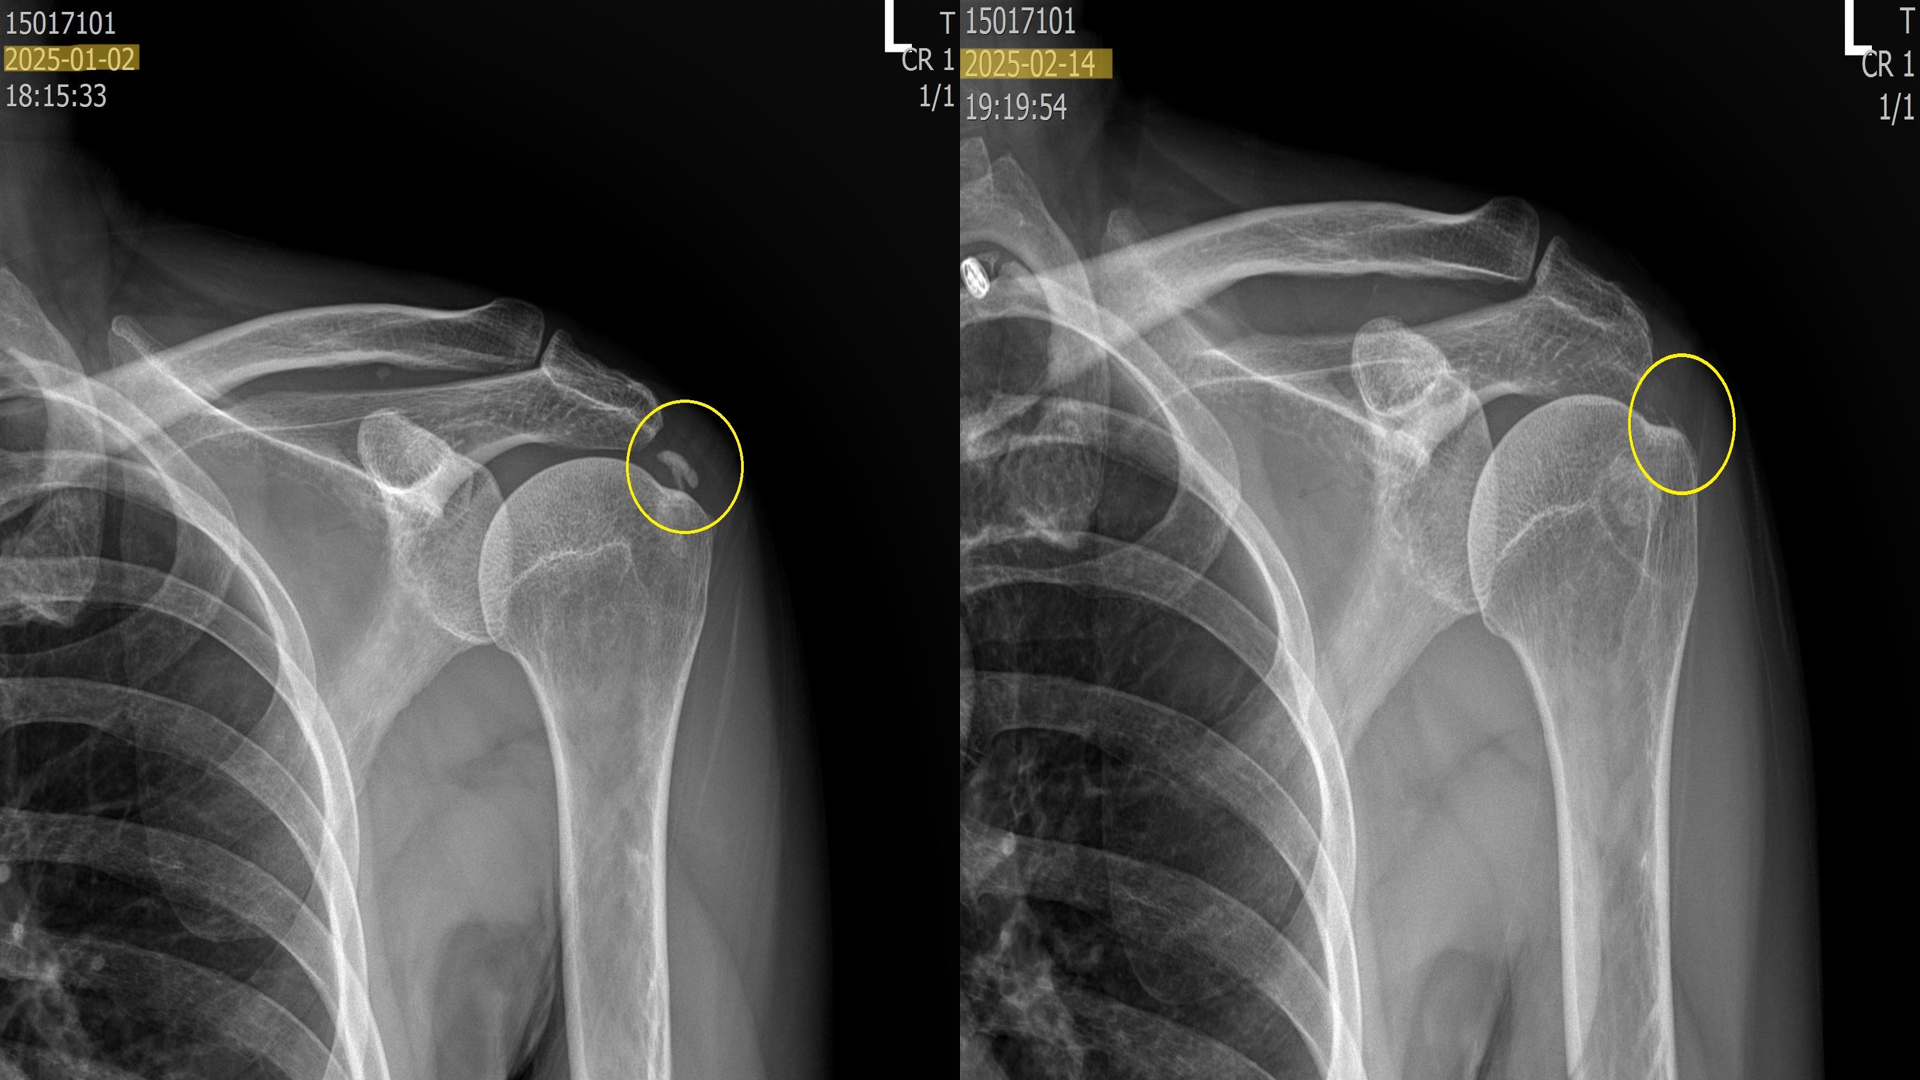

위의 사진은 실제로 내원하여 치료받은 환자들의 x-ray 입니다. 이 환자분들은 약 5회에 걸쳐 섭회흡입술 + 체외충격파시술을 받은 분들입니다. 보시다시피 드라마틱하게 석회가 제거된걸 볼 수 있습니다.